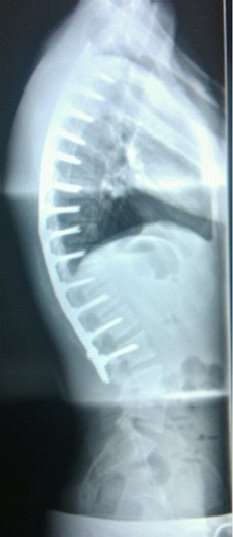

![]() A 24-year-old male showing a normal kyphosis curve after a 13-level spinal fusion to correct Scheuermann's disease | |